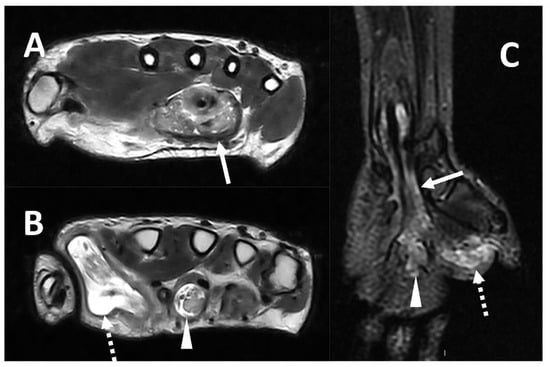

2.3. Soft-Tissue Foreign Body

- Carneiro, B.C.; Cruz, I.A.N.; Chemin, R.N.; Rizzetto, T.A.; Guimarães, J.B.; Silva, F.D.; Junior, C.Y.; Pastore, D.; Ormond Filho, A.G.; Nico, M.A.C. Multimodality imaging of foreign bodies: New insights into old challenges. Radiographics 2020, 40, 1965–1986. [Google Scholar] [CrossRef] [PubMed]

- Jarraya, M.; Hayashi, D.; de Villiers, R.V.; Roemer, F.W.; Murakami, A.M.; Cossi, A.; Guermazi, A. Multimodality imaging of foreign bodies of the musculoskeletal system. AJR Am. J. Roentgenol. 2014, 203, W92–W102. [Google Scholar] [CrossRef] [PubMed]

- Peterson, J.J.; Bancroft, L.W.; Kransdorf, M.J. Wooden foreign bodies: Imaging appearance. AJR Am. J. Roentgenol. 2002, 178, 557–562. [Google Scholar] [CrossRef] [PubMed]

- Johnson, P.W.; Collins, M.S.; Wenger, D.E. Diagnostic utility of t1-weighted mri characteristics in evaluation of osteomyelitis of the foot. AJR Am. J. Roentgenol. 2009, 192, 96–100. [Google Scholar] [CrossRef]

| Wood | 36% of FBs in hand injuries Only 25% of patients note penetrating injury | Radiolucent | 50–80 HU | Hyperechoic with posterior acoustic shadow; possible reverberation related to gas content | Low T1 and T2; surrounding inflammatory change and enhancement |